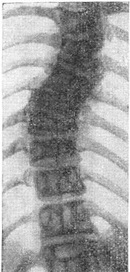

![]() Рис. 12. Бічний клиновидний напівхребець. |

Бічні клиновидні хребці, або полупозвонки (рис. 12), відносяться до порівняно нередкому виду аномалій. Вони частіше бувають поодинокими або подвійними. В останньому випадку клиноподібні полупозвонки розташовані з протилежних сторін, і їх називають альтернирующими (рис. 13). Зрідка зустрічаються подвійні односторонні полупозвонки. Бічні клиноподібні полупозвонки є однією з причин вродженого сколіозу. Особливо несприятливі в цьому відношенні подвійні односторонні полупозвонки.